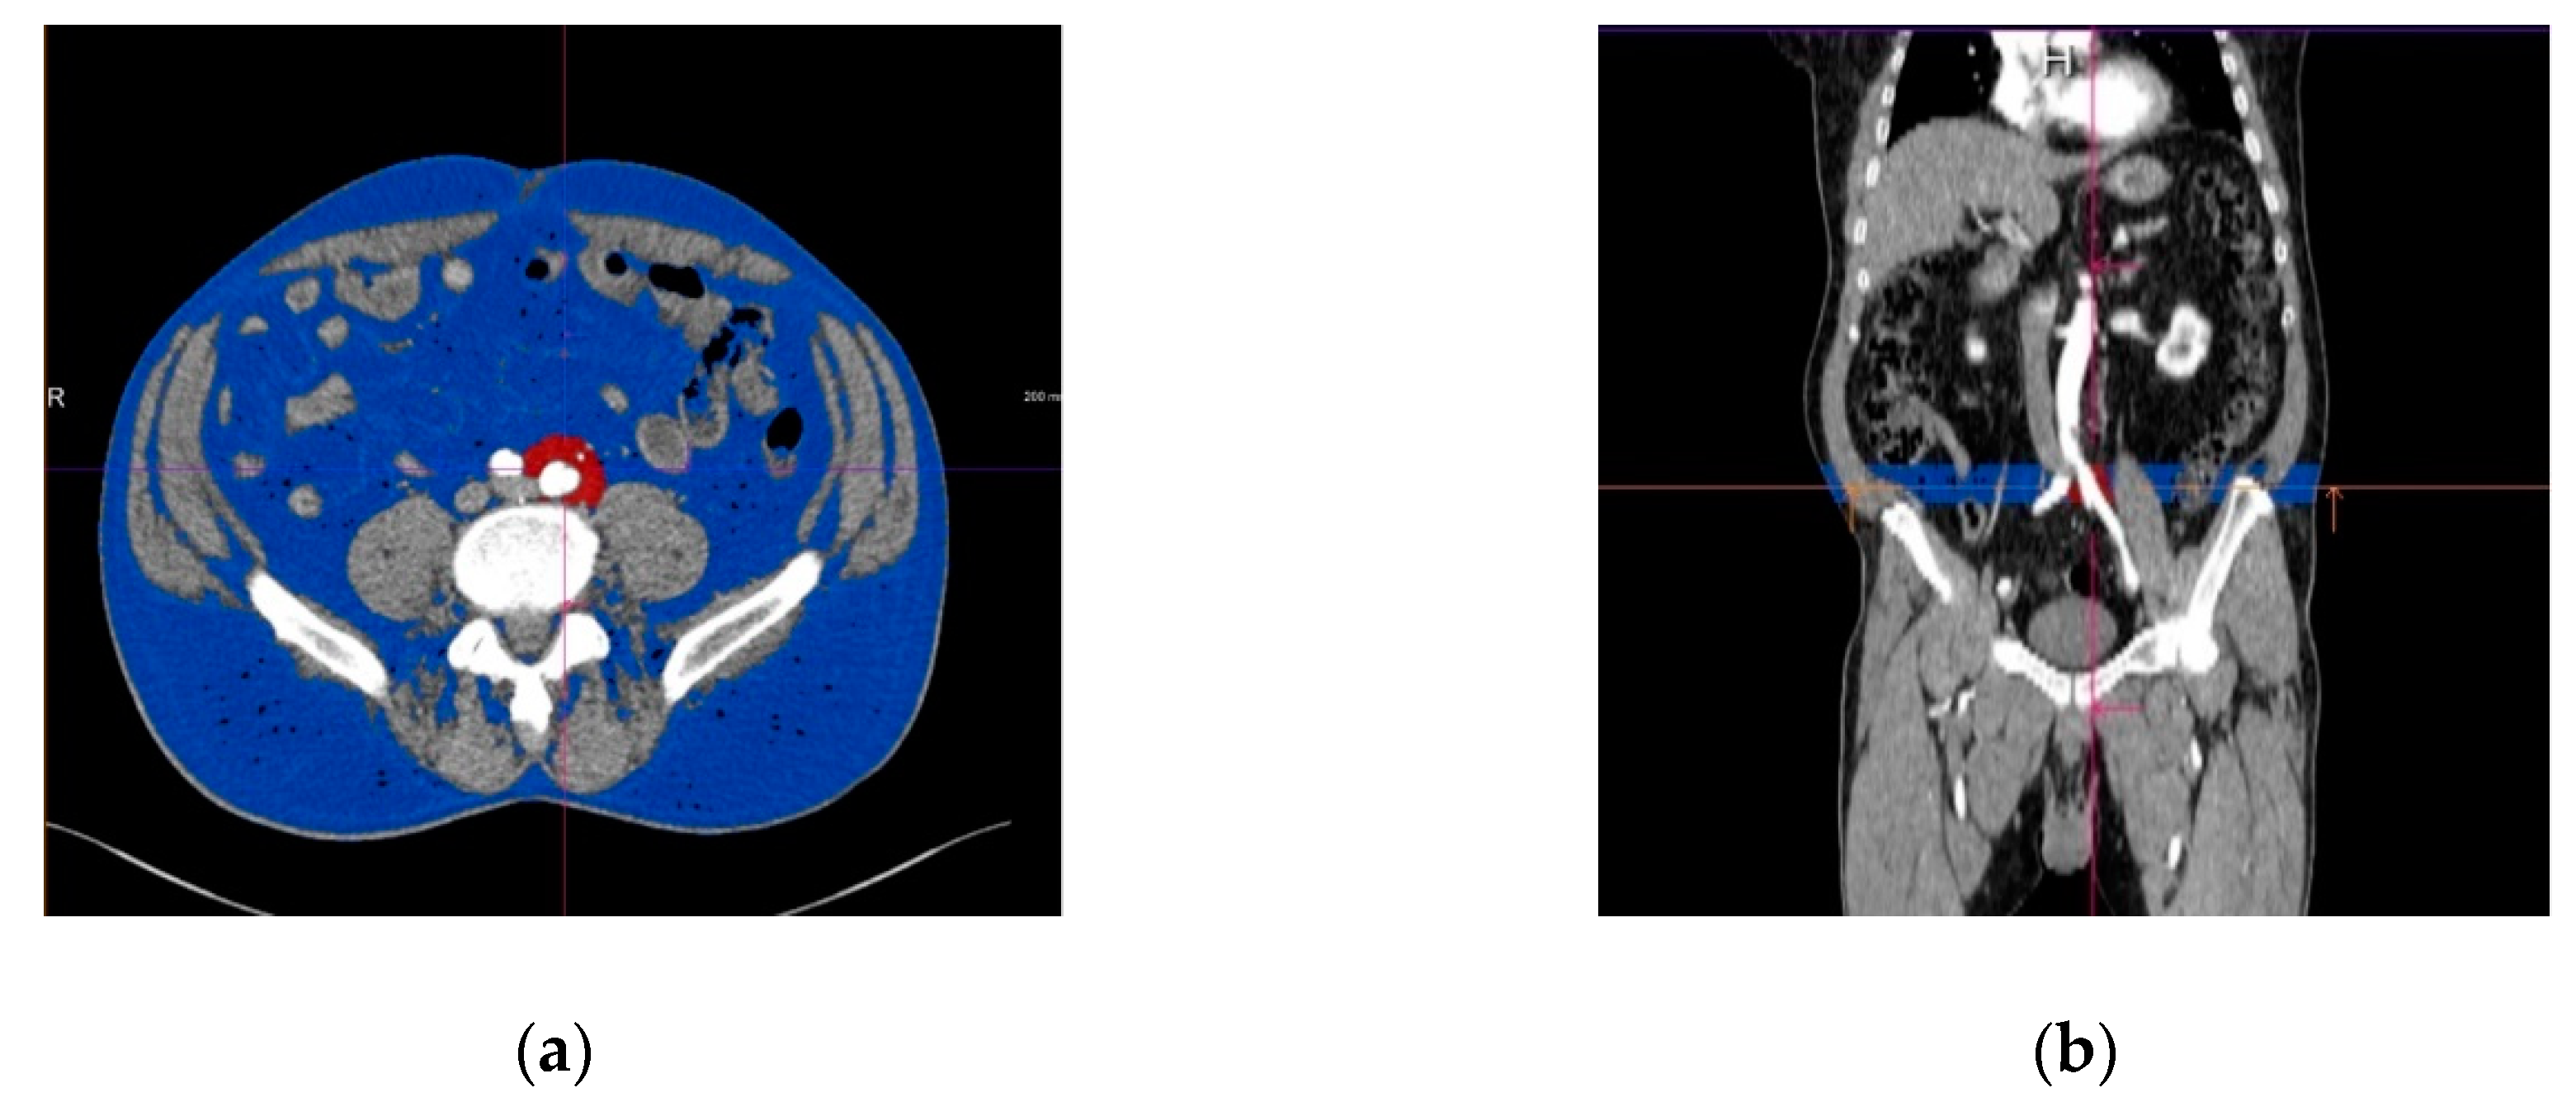

2.2. Computer-Aided CT Image Postprocessing

2.3. Assessment of the Periiliac Adipose Tissue

2.4. Assessment of The Subcutaneous and Visceral Adipose Tissue